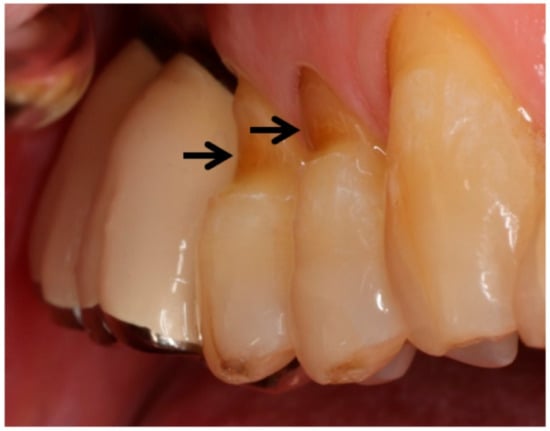

- Yoshizaki, K.T.; Francisconi-dos-Rios, L.F.; Sobral, M.A.P.; Aranha, A.C.C.; Mendes, F.M.; Scaramucci, T. Clinical Features and Factors Associated with Non-carious Cervical Lesions and Dentin Hypersensitivity. J. Oral Rehabil. 2017, 44, 112–118. [Google Scholar] [CrossRef] [PubMed]

- Grippo, J.O. Abfractions: A New Classification of Hard Tissue Lesions of Teeth. J. Esthet. Restor. Dent. 1991, 3, 14–19. [Google Scholar] [CrossRef]

- Grippo, J.O.; Simring, M.; Schreiner, S. Attrition, Abrasion, Corrosion and Abfraction Revisited: A New Perspective on Tooth Surface Lesions. J. Am. Dent. Assoc. 2004, 135, 1109–1118. [Google Scholar] [CrossRef]

- Grippo, J.O.; Simring, M.; Coleman, T.A. Abfraction, Abrasion, Biocorrosion, and the Enigma of Noncarious Cervical Lesions: A 20-Year Perspective. J. Esthet. Restor. Dent. 2012, 24, 10–23. [Google Scholar] [CrossRef]

- Wood, I.; Jawad, Z.; Paisley, C.; Brunton, P. Non-Carious Cervical Tooth Surface Loss: A Literature Review. J. Dent. 2008, 36, 759–766. [Google Scholar] [CrossRef]